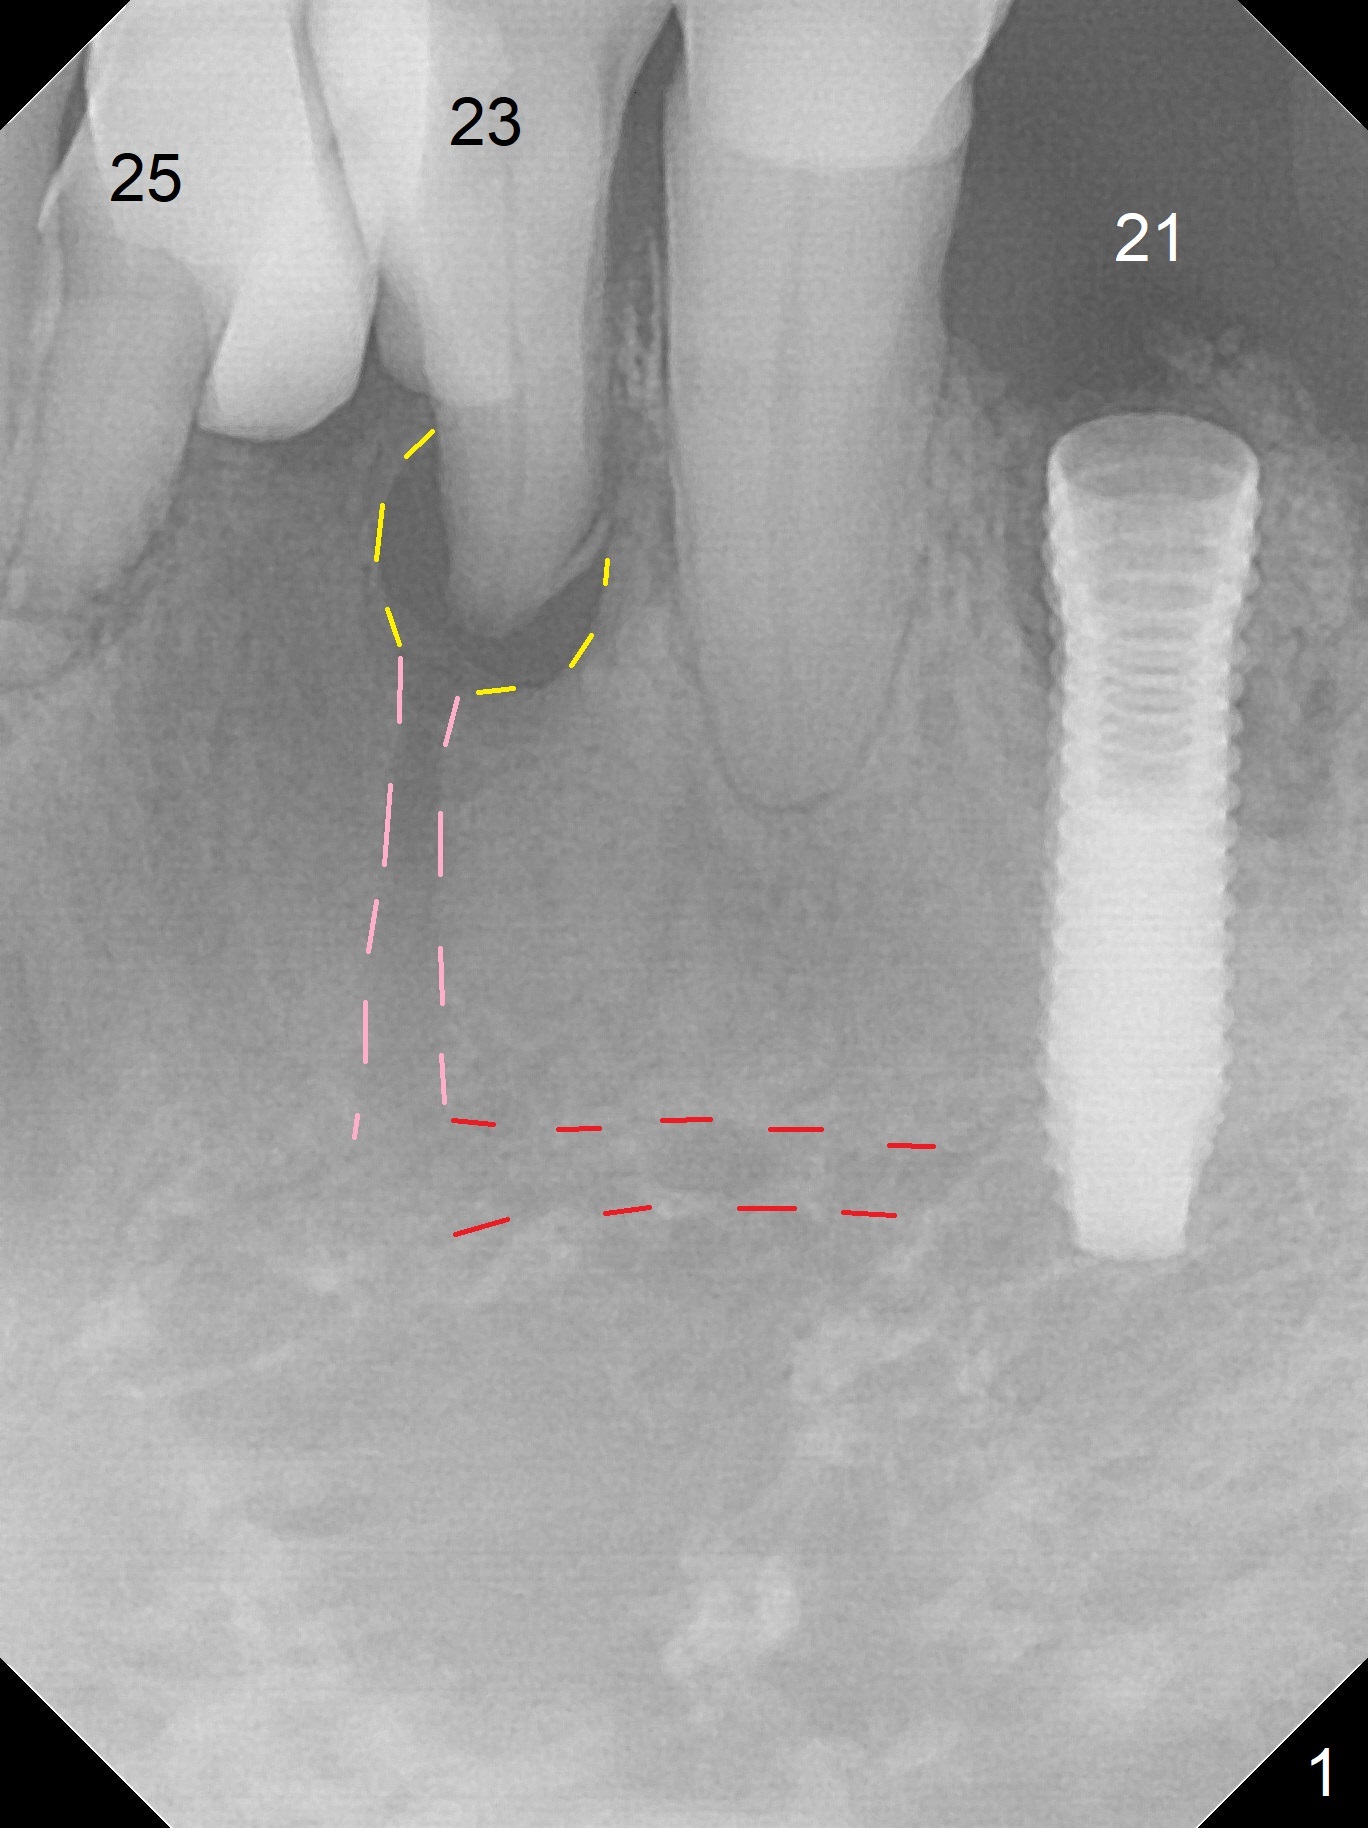

A 73-year-old man will return for #23 and 25 implants following ones at #21 and 31. Probably due to large periapical radiolucency at #23 (Fig.1 yellow dashed line), the terminal branch (pink) of the Incisive Canal (red) is distinct. Postop hemorrhage occurs associated with placement of a long implant at #. To prevent the complication at #23, a 14 mm long 1-piece implant (Fig.3) seems to be safer than 16 mm one (Fig.2). Seven mm in the native bone (Fig.3) should provide with sufficient primary stability. A temporary crown will be fabricated at #31. If the provisional at #21 is unstable, impression may be necessary for #21 and 31. Initiate osteotomy using visual and tactile acuity and double check the position and trajectory with RPD and X-ray. It might be preferable to extract the malpositioned incisor to give the remaining one the best 3-dimensional reference. Prepare 2 of 1-piece implant kits as well as angled one.